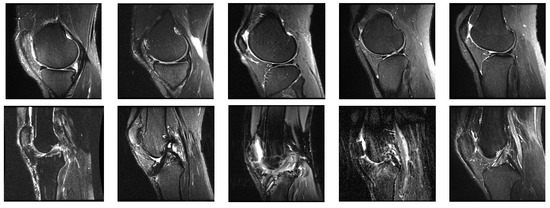

4.1. System Configurations and Dataset